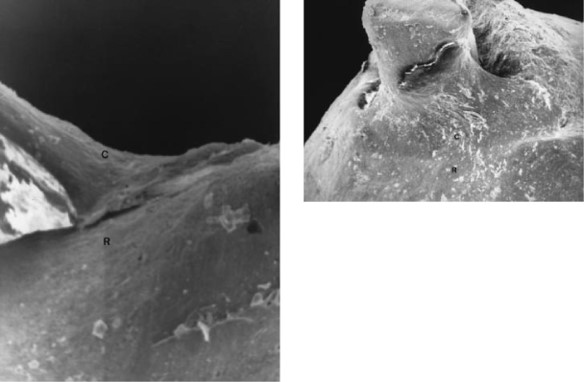

The SEM examination revealed the presence of calcified tissue extending from the surface of the root around the apex to the extruded gutta-percha cone, forming a bridge between them (Fig. 3). A clear contact line was noticed between the newly formed tissue and the apex (Fig. 4). The surface of this tissue was smooth and had a similar appearance to the surface of the cementum of the root to which it appeared to be tightly attached (Fig. 5). The formed tissue adapted closely to the extending gutta-percha but small voids were also observed. The remainder of the surface of the root around the apex had a rough appearance (Fig. 3).Despite 4-5 mm of gutta-percha that were pushed into the periradicular tissues and the fmal 1 min overfill, there was healing of the periradicular tissues 4 years after the completion of the root canal treatment and the patient remained asymptomatic. The case was considered successful according to the criteria for evaluating the success of endodontic therapy (Bender et al. 1966).

In teeth of animals with induced periapical lesions, cementum deposition was apparent at the root apex 12 weeks after root canal treatment. This deposition was considered as early histological proof of healing (Fouad et al. 1993). Deposition of hard tissue has also been demonstrated histologically in the root canal space of overinstrumented and underfilled root canals in animals (Davis et al. 1971, Benatti et al. 1985). Ad-ditionally, in long-term follow-up radiographs of successful cases of root-canal-treated teeth with periapical lesions and apical resorption, cementum deposition is obvious at the root apex (Weine 1996). In the present case the SEM examination of the extracted root revealed evidence of deposition of hard tissue at the root apex despite the fact that there was overfilling. This tissue resembled the cementum of the root and appeared to be calcified. Furthermore, it seemed to be tightly attached to the surface of the cementum and it adapted closely to the overextended gutta-percha. The rough appearance of the rest of the root surface around the apex led to an assumption that, on this rough surface, more of this tissue may have been attached and had possibly been destroyed during the extraction of the root. Although a histological examination of this newly formed hard tissue was not performed, it is believed to be secondary cementum which was deposited in the areas of the root resorption. Possibly this deposition constituted an effort by the local defence mechanisms of the periapical tissues to isolate the foreign materials (gutta-percha and sealer). Finally, although in the postoperative radiograph the root canal filling in the apical third appears to be complete, in the SEM photographs a gap is evident between the newly formed tissue and the gutta-percha master cone. This gap was possibly created when the tooth was extracted or during specimen preparation for the SEM. In conclusion, although there was substantial extrusion of filling materials in the periapical area, long-term healing with secondary cementum deposition at the apex and resolution of lesion occurred and the case was considered to be successful. Obviously, these findings should not encourage dentists to overfill root canals, but they confirm the importance of chemomechanical preparation and complete obturation of the root canal, as well as the low toxicity of gutta-percha.